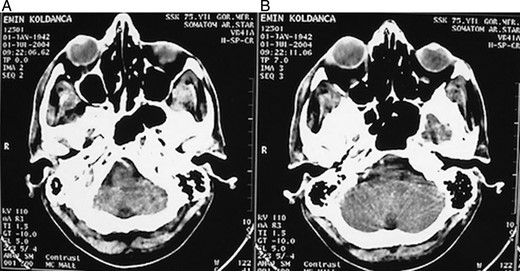

A 62-year-old male patient referred to our clinic due to painless exophthalmia of his right eye for the last 2 years. On neurological examination of the patient, there was no abnormality except for the up-gaze restriction and severe exophthalmia. Computerized tomography revealed an intraorbital mass in the right eye. A well-defined 2.5-cm isodense mass was located on the right lacrimal gland. The mass was contrasted homogenously (Fig. 1a and b). Cranial magnetic resonance imaging (MRI) revealed an isointense mass on the superolateral part of right orbita in the coronal intersections and it was contrasted homogenously (Fig. 2a and b). The existing score of our patient according to Rose and Wright was +8 points. Combined orbitofrontal craniotomy was performed through a transcranial approach. The well-defined, soft, white, 2.5-cm mass was removed completely. Exophthalmoses disappeared after the surgery (Fig. 3a and b). Histological examination of the surgical specimen covered the epithelial and stromal components that formed the glandular structures. Keratinized plugs were seen in some glandular lumens. Cartilaginous differentiation of stroma was found (Fig. 4a–d). Based on these findings, the tumor was diagnosed as pleomorphic adenoma. There was no recurrence after 8-year clinical follow-up.

(A and B) Postoperative computerized tomography revealed the replacement of the eye.